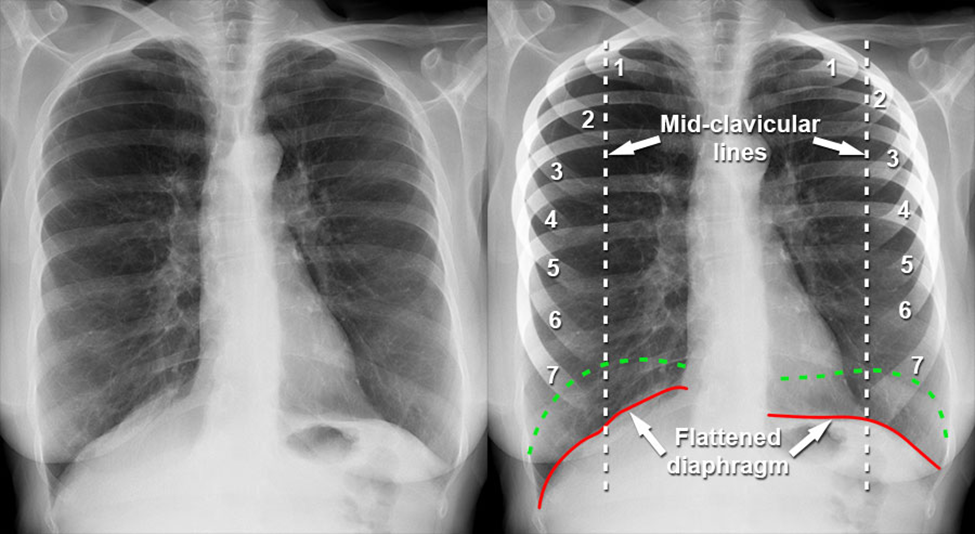

Sự tăng thể tích phổi kéo dài này gây ra hàng loạt thay đổi về hình thái lồng ngực [3]. Cơ hoành, vốn có dạng vòm để tối ưu hóa lực co cơ, bị đẩy xuống thấp và trở nên dẹt hơn do phổi luôn ở trạng thái “căng”.

Nguồn: Radiopaedia.org – COPD with hyperinflation and flattened diaphragm (case illustration).

Khi cơ hoành mất đi độ cong sinh lý, hiệu quả co bóp giảm rõ rệt, buộc bệnh nhân phải huy động thêm các cơ hô hấp phụ ở cổ và vai để duy trì thông khí. Đồng thời, các xương sườn dần nằm ngang hơn thay vì chếch xuống dưới như bình thường, làm tăng đường kính trước – sau của lồng ngực [3]. Lồng ngực vì thế trông giống như đang giữ ở tư thế hít vào liên tục, tạo nên hình ảnh đặc trưng của lồng ngực hình thùng.